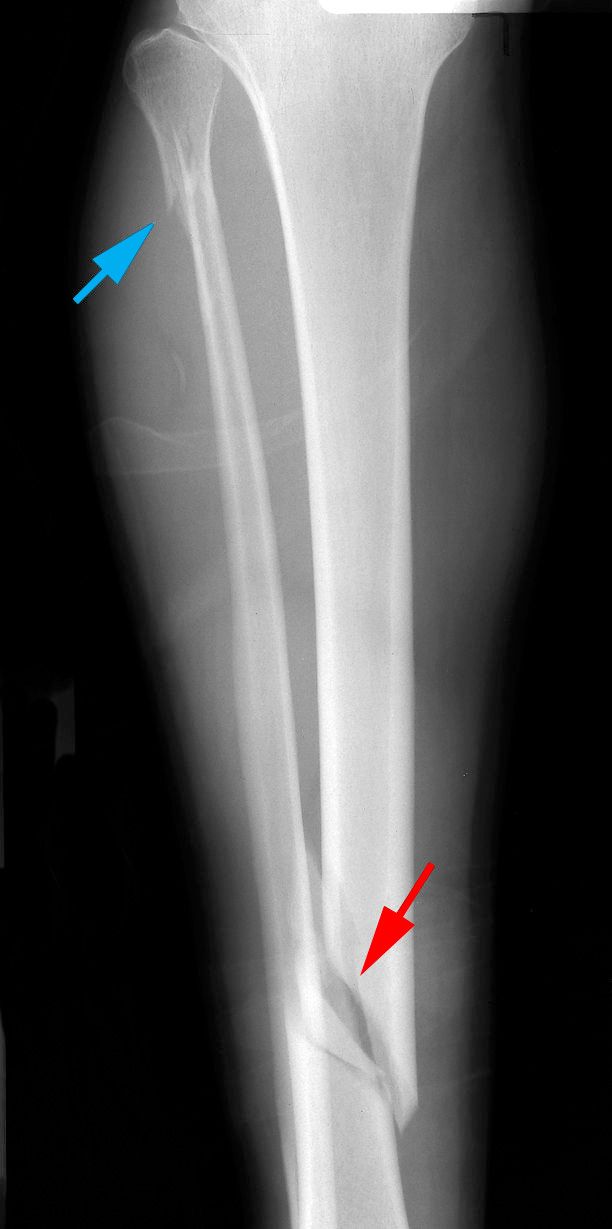

X-rays. The most common way to evaluate a fracture is with X-rays, which provide clear images of dense structures like bones. X-rays can:

• Show whether the tibia is broken or intact

• Show the type of fracture and where it is located within the tibia

• Help identify the involvement of the knee or ankle joints

• Show whether there is also a fibula fracture

Oblique tibial shaft fracture

X-ray shows an oblique (angled) fracture of the tibial shaft (red arrow). The patient’s fibula was also fractured during the injury (blue arrow).

Reproduced from Johnson TR, Steinbach LS (eds.): Essentials of Musculoskeletal Imaging. Rosemont, IL. American Academy of Orthopaedic Surgeons, 2004, p. 504.